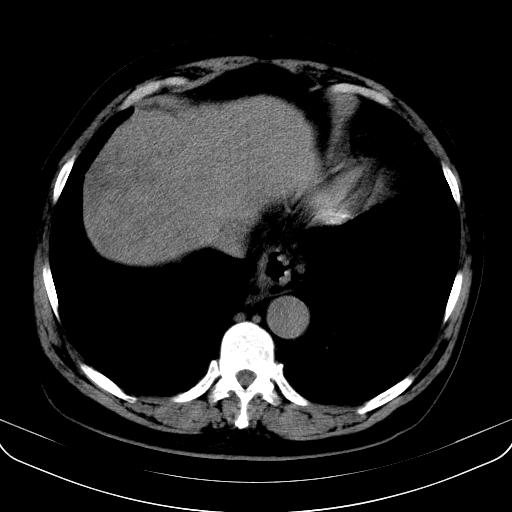

以下是引用jia119在2008-3-5 13:31:00的发言:[br]肝内多发片状低密度影,密度不均,我还是考虑肝ca可能,另肝内小囊肿,胆囊增大。

以下是引用形影不离在2008-3-5 12:18:00的发言:[br]肝硬化伴门脉高压征,肝内占位待排,增强再说.

以下是引用随光逐影在2008-3-5 21:11:00的发言:[br]肝硬化伴门脉高压(食管下段静脉曲张),肝癌不排除。建议:行ct增强扫描检查。

以下是引用同在2008-3-5 13:56:00的发言:[br]考虑肝癌可能性大,胆囊增大.